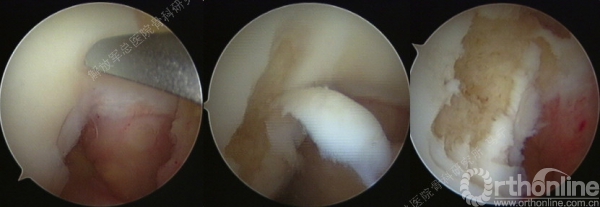

第一次手术-评估(关节镜评估及取种子细胞)。

缺损部位的标记:根据关节镜下的检查评估来确定损伤部位,范围,以决定二次手术的切口部位。

软骨组织的获取:关节镜下观察关节软骨的股骨髁间非负重区的穹窿部位或股骨滑车区边缘非负重部位,清理周围的滑膜组织,应用髓核钳或鹅眉凿获取患者关节软骨100-200mg

切开后可以看见很明显的软骨破坏。

对糜烂的软骨进行清创,按照损伤的面积裁剪软骨补片进行修补。